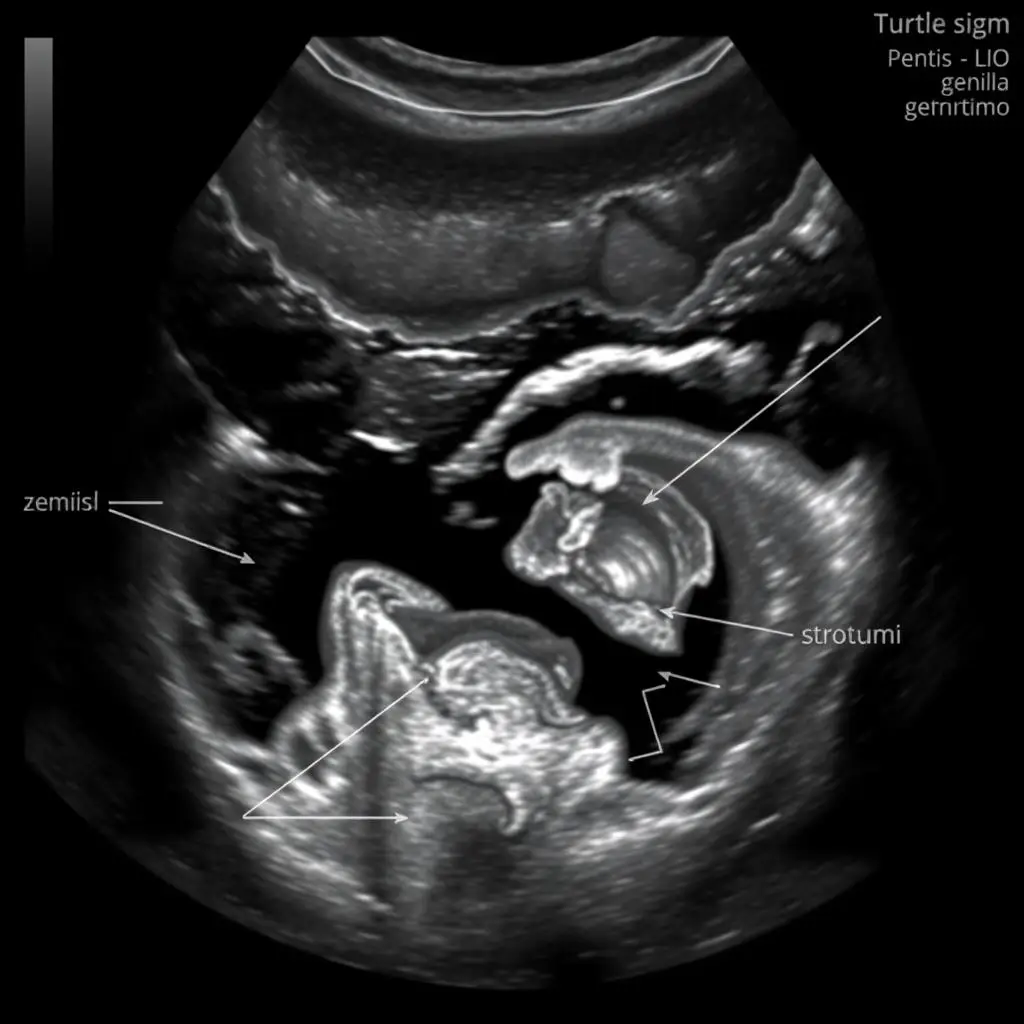

Rozpoznanie chłopca

U chłopców charakterystycznym obrazem jest tzw. „znak żółwia” lub „znak trzech linii”, gdzie widoczny jest penis i moszna. Narządy płciowe męskie są wypukłe i wystające, co ułatwia ich identyfikację. Już w 14-16 tygodniu ciąży doświadczony lekarz może zauważyć te struktury, jednak pewniejsza ocena jest możliwa od 18. tygodnia [7].

USG ukazujące narządy płciowe męskie – „znak żółwia”